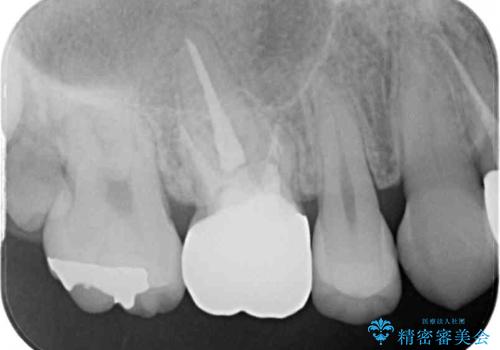

- 虫歯により神経を取り除いた前歯の変色が気になるとのことで来院された患者様です。

レントゲン写真より、歯根の炎症が認められなかったため、ファイバーコアによる土台築製後、オーダーメイドタイプのオールセラミッククラウンにて補綴することとしました。